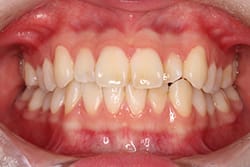

• Case1

歯のガタガタを治したい

Before

After

年齢

20代女性

治療期間・回数

約1年6ヶ月間、18回

費用

総額990,000円(税込み)

(検査・診断・マウスピース費用・管理費・通院費全て含む) ※自由診療となります。

リスク・副作用

歯の動きには個人差があり、痛み・口内炎・歯肉退縮・歯根吸収・隙間・補綴物の外れなどが生じる可能性があります。装着時間や来院状況が結果に影響します。